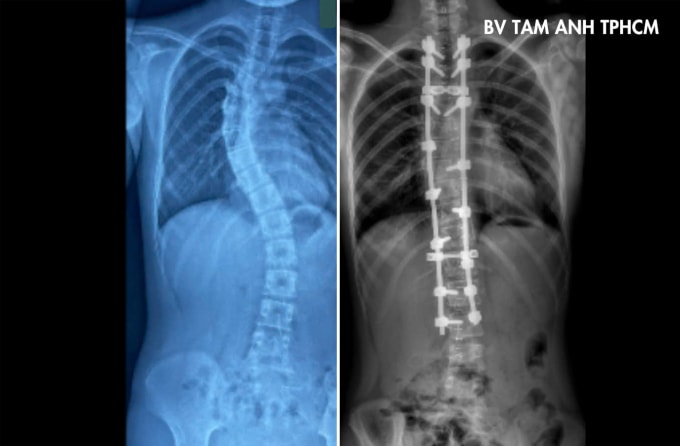

Sophea điều trị tại Campuchia hơn một năm, nay sang Việt Nam phẫu thuật. Kết quả chụp X-quang tại Bệnh viện Đa khoa Tâm Anh TP HCM cho thấy đoạn từ đốt sống ngực thứ 4 đến thứ 10 vẹo sang phải 57 độ, từ đốt sống ngực thứ 10 đến đốt sống lưng thứ 3 vẹo trái 40 độ, có dấu hiệu chèn ép phổi. Hai vai bệnh nhi lệch nhiều, gù lưng, khó rướn người, đau khi vận động mạnh.

Sau 4 giờ, 16 vít được sử dụng để nắn chỉnh phần cột sống trên về 17 độ và cột sống dưới về 15 độ. Ngày thứ hai sau mổ, Sophea có thể tự đi lại, hai vai cân bằng và dáng đi cải thiện rõ rệt. Tiên lượng sau hai tuần, bệnh nhi có thể sinh hoạt như bình thường. Bác sĩ khuyến khích bé tham gia các môn thể thao như đu xà, bơi lội, tránh các môn có tính đối kháng, và sinh hoạt đúng tư thế để tránh cong vẹo cột sống tái phát hoặc mắc biến chứng đau lưng sau mổ.